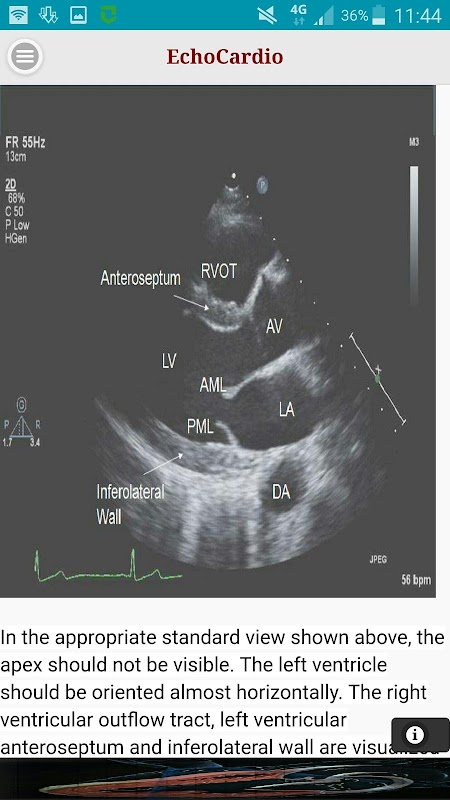

Parasternal lange Achse